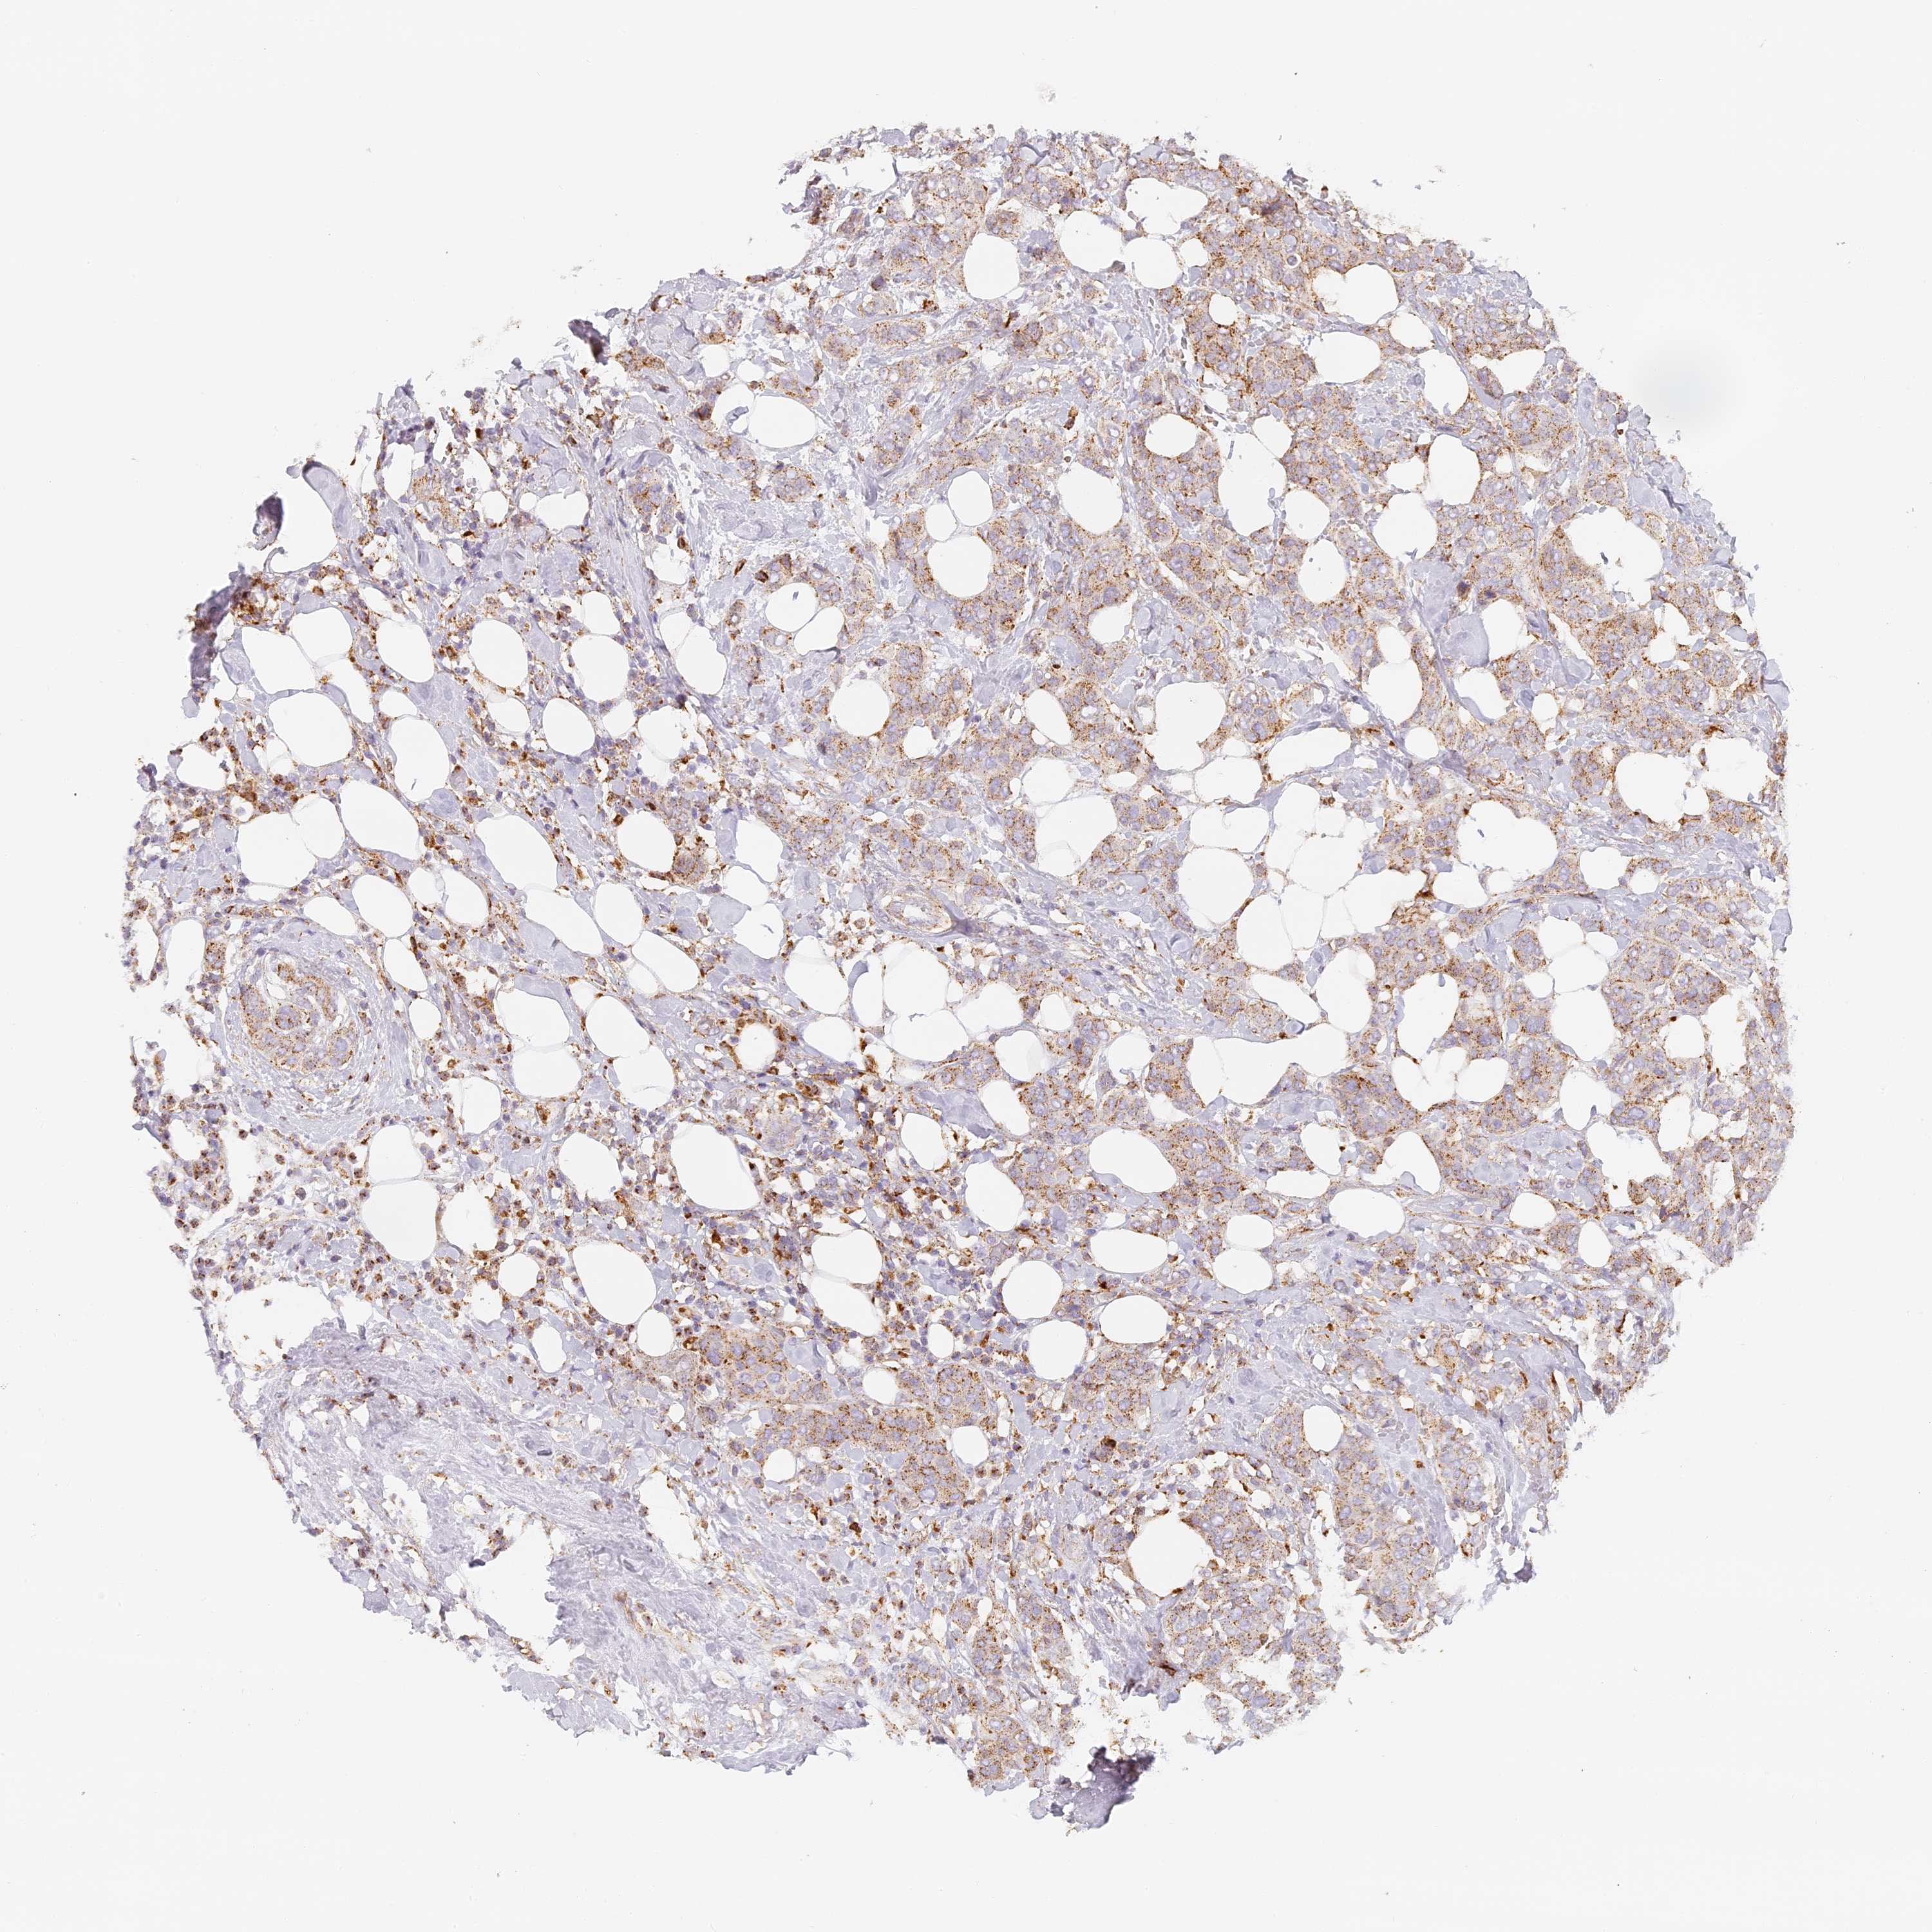

CANCER BREAST CANCER Show tissue menu

BRCA TCGA BRCA VALIDATION PROTEIN EXPRESSION